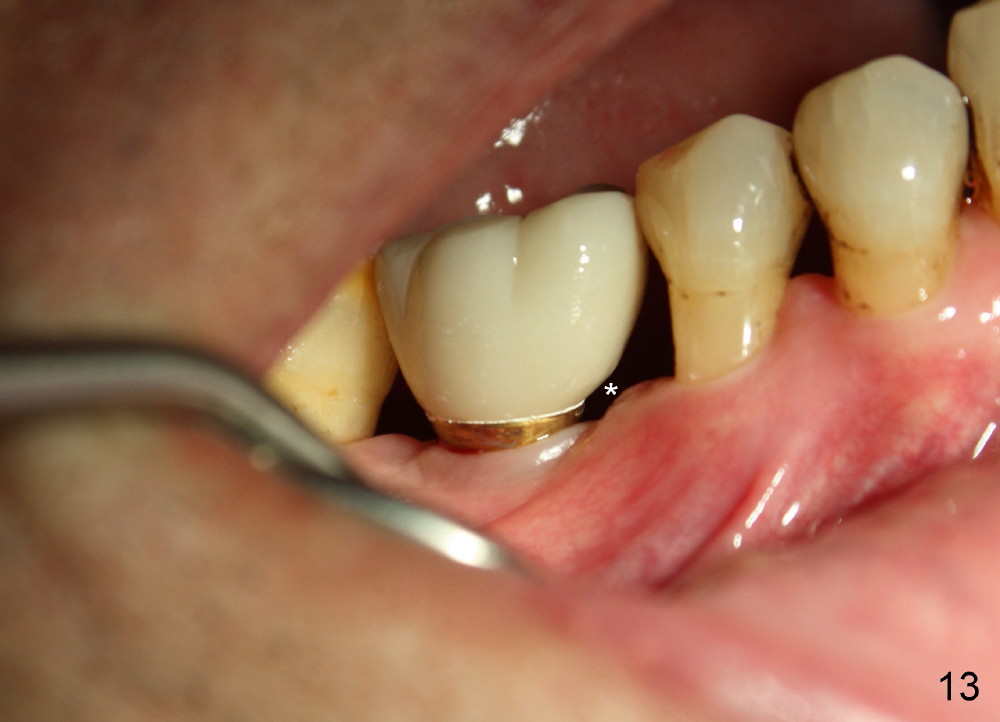

When a positioning pin is placed in the osteotomy with 10 mm deep, the sensor cannot be placed deep enough because of pin interference so no IAC is visible (Fig.4). When the pin is removed and the sensor is placed low enough, IAC is clearly shown, but the osteotomy is barely visible (Fig.5 pink dashed line). With information obtained from pre- (Fig.2,3) and intra- (Fig.4,5) op PA, twelve mm of osteotomy appears to be appropriate. A final implant (5.3x12 mm) is placed with separation from IAC (Fig.6, insertion torque 50 Ncm). A healing abutment is placed (Fig.7,8), which helps retain perio dressing (Fig.9). Two weeks later, the gingiva heals around the abutment (Fig.10). Four months postop, the implant appears to osteointegrate (Fig.11). A cemented abutment is placed (Fig.12). With supragingival margin, oral hygiene is easily maintained (Fig.13). Due to delayed placement, the gingival embrasure is extremely large (*). The issue is much less with immediate implant.